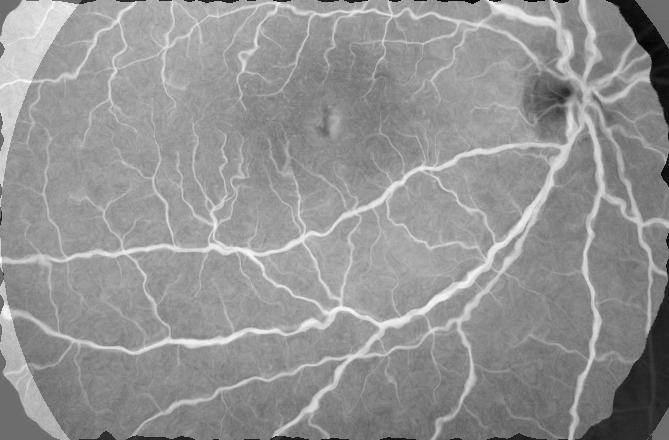

Table 1 shows the registration performance for , our proposed method, and compared with the following methods: - the CNN based registration method of [28]; - an iterative NMI based registration method [85, 86, 87, 88, 89, 90, 91]; and - without deformation consistency constraints. has the best performance across all metrics. Figure 2 shows registration results for retinal images. registers the images closest to the original and is able to recover most deformations to the blood vessels, followed by , , and . It is obvious that deformation reversibility constraints significantly improve registration performance. Note that the fundus images are color while the FA images are grayscale. The reference image is a grayscale version of the fundus image.

| (a) | (b) | (c) | (d) | (e) | (f) | (g) | (h) |